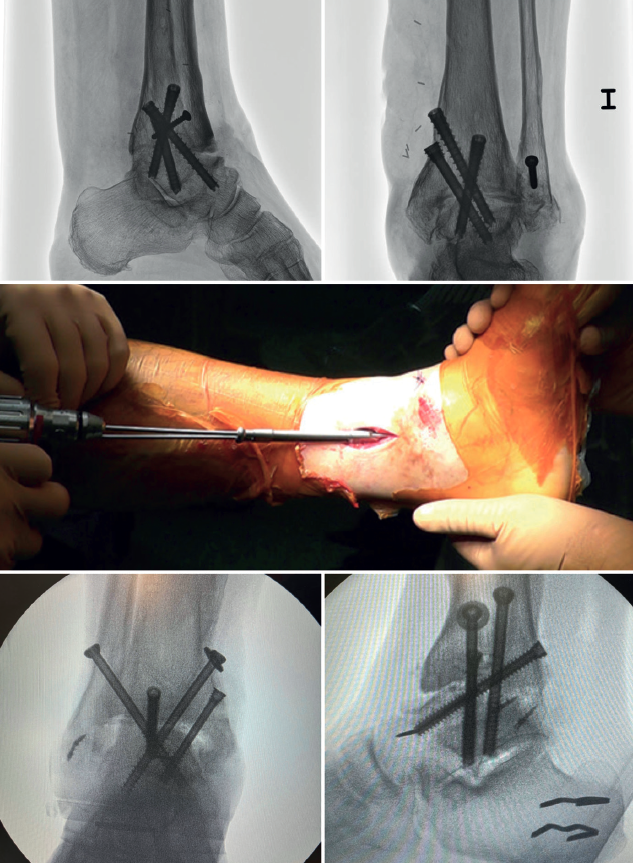

In arthroscopic ankle arthrodesis, the use of percutaneously placed compression screws is the technique of choice (Figure 5).

Most authors consider the use of cannulated screws (3 to 4) to be the ideal fixation method. The diameters of the chosen screws should be between 6 and 7 mm. This technique achieves 85-100% fusion and 84-95% patient satisfaction rates(19).

Van Dijk, Kerkhoffs et al.(20) reported excellent results with the use of three screws as the standardized method for ankle arthrodesis.

Screw configuration and placement

Depending on the deformity involved and according to preoperative planning, screw placement is carried out starting with the compression screw that counteracts the deformity.

In other words, in arthropathies with a varus component, we would start with a lateral screw, while in valgus misalignments the recommendation is to place the first screw from the medial side. The second screw should be on the side opposite to the first. Both should provide adequate compression between the joint surfaces(17).

In general, a minimum of three screws are used. The third screw is the so-called home run screw, the importance of which has been highlighted by Holt et al.(21). It is directed across the ankle from the posterior part of the tibia to the neck of the talus. A fourth screw may be used as an augmentation of the first, counteracting the main deformity.

Goetzmann et al.(22), in their review of 111 cases, supported the use of at least three screws for fixation of arthroscopic tibiotalar arthrodesis. The addition of a third screw appears to be associated with a lower risk of pseudarthrosis and shorter consolidation time. These effects can be attributed to an increased stability of the construct.

Glick, Myerson(23)et al. reported that the configuration conferring the greatest rigidity to the osteosynthesis comprises two screws from medial and one from the lateral side.

In cases where there is anterior translation of the talus, good resection of the posterior tibial malleolus is important to allow for reduction and proper positioning of the talus. Another useful technique is, in the supine position, to place a support under the distal tibia leaving the heel free to be manually moved posteriorly.

In some of these cases with anterior translation of the talus, and contrary to the usual recommendations, it may be useful to first position the posteroanterior screw with partial threading, to reduce the talus from anterior to posterior and align it with the lateral longitudinal axis.

Definitive anteroposterior, mortise, lateral ankle, dorsoplantar and oblique foot radiographs are obtained to confirm correct reduction, and the position and length of the screws, especially the home run screw (Table 3).